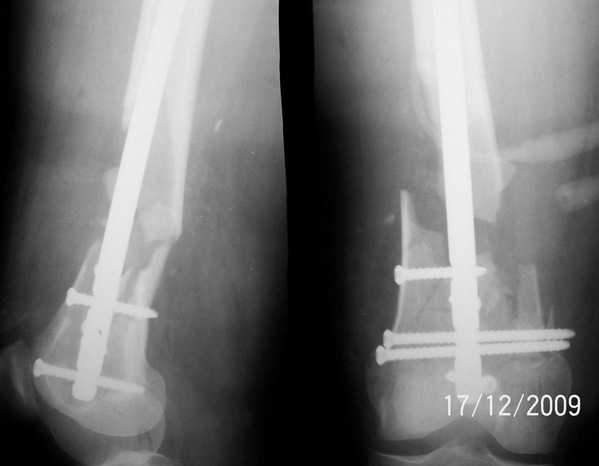

Уважаемые коллеги, прооперирована пациентка антеградным штифтом Остеомед, костная пластика не проводилась. Выбранный штифт по каналу бедренной кости на фоне отсутствия переднего кортикала в канале не центрируется. Технически неприятно, отсутствие передней и внутреннебоковой стенки до зоны мыщелков сильно затрудняло репозицию. Получилась вот такая картина. После стабилизации - очевидное повреждение ПКС и боковая нестабильность. В общем и далее будет чем заняться. Нам и в дальнейшем будет очень интересно мнение коллег.

|

Молодцы, здорово получилось. Как ввдили самый дистальный винт? Надколенник не мешал?

А надколенник мешал слегка, но... штифт слегка предмоделирован до начала операции и угол введения дистального винта был градусов на 15 изменен, в итоге серьезной помехи надколенник не создал.

Общее время нахождения в операционной составило около 3,5 часов, бедро заняло около 2-х. У больной имелся также перелом в/3 костей контрлатеральной голени, там тоже пришлось помучиться, репозиция была не без проблем), остеосинтез проксимальным эскпертом остеомед. Работа ЭОПа составила около 5 минут.

Повторюсь - "Выбранный штифт по каналу бедренной кости на фоне отсутствия переднего кортикала в канале не центрируется", при устранении угловой деформации штифт фактически не попадал в дистальный отломок, отсюда и мучения...

Обычное время работы ЭОПа про отсутствии каких-либо интраоперационных проблем при интрамедуллярном остеосинтезе не превышает одной минуты.